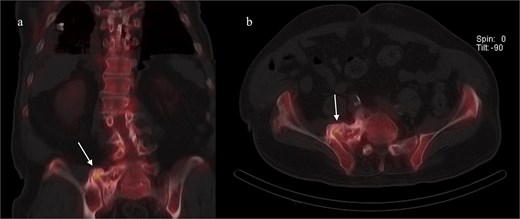

He was discharged home on postoperative day two, with instructions to remain toe-touch weight-bearing for three weeks. He was seen in the office two weeks after surgery. Lateral and antero-posterior pelvic radiographs showed good position of all hardware (Fig. 4). He reported mild incisional pain, but his preoperative pain had significantly improved. He was able to ambulate for the first time in years. Pain relief remains sustained three months after surgery.

Postoperative lateral (left) and AP (right) re-demonstrated good placement of the hardware.